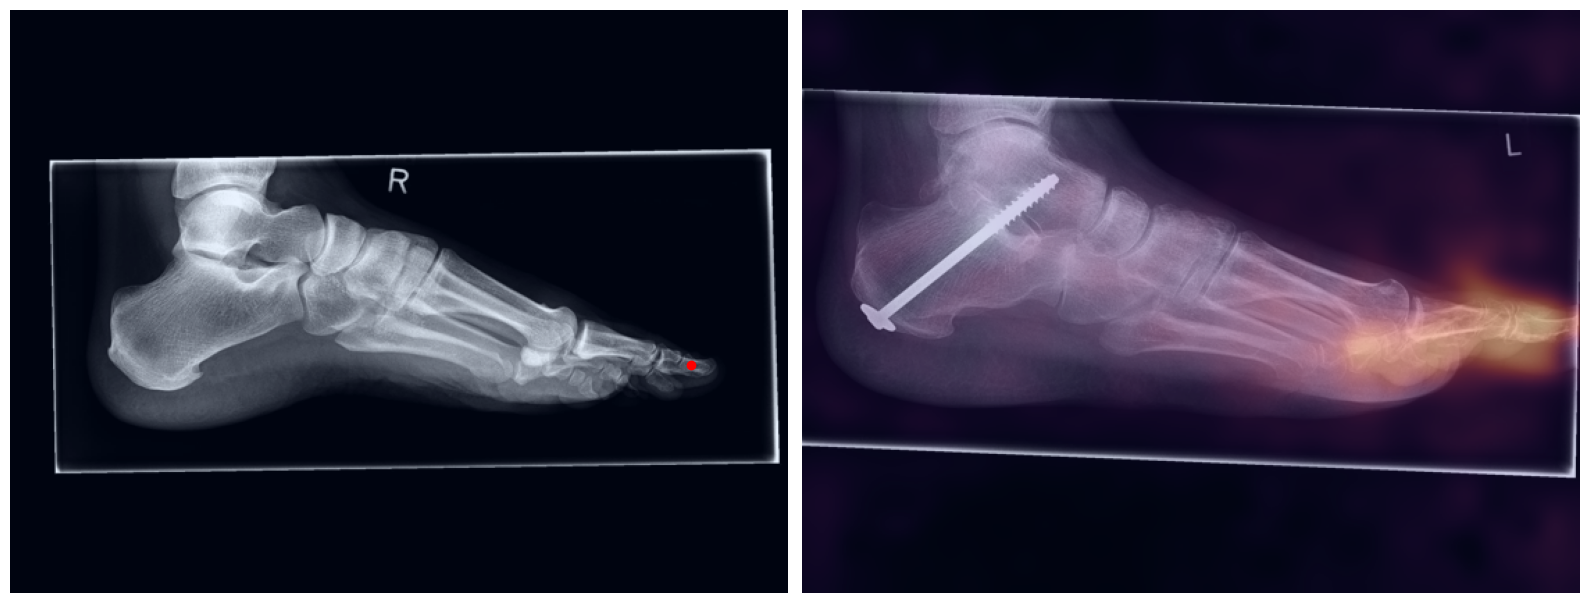

This study presents a zero-shot artificial intelligence (AI)-based approach for automated landmark matching in radiographs, designed to improve scalability and reliability in deriving musculoskeletal (MSK) measurements across various anatomic regions and conditions. Key anatomic landmarks were manually identified under expert supervision, building the basis to automatically derive pertinent angle and distance measurements. Using one patient's radiograph as a reference, a robust AI-based feature matching approach establishes dense matches between the reference and unseen target images. Reference landmarks are transferred along the dense matching, resulting in precise landmark placement and automated calculation of MSK measurements within an entire patient cohort. The results demonstrate versatile and robust application without requiring anatomy-specific training, while remaining stable with in the presence of orthopedic implants.

Artificial intelligence (AI) has shown great potential in assisting radiologists with musculoskeletal (MSK) assessments across various anatomical regions1,2,3,4. However, most existing tools are narrowly tailored for specific anatomies or rely on segmentation-based methods as a basis. To address these limitations, we propose a versatile and generalist AI-based approach for landmarks matching. In contrast to typical generalist landmark matching approaches that depend on automatically identified, optimally descriptive landmarks5,6,7, our use-case has to be based on manually selected landmarks tailored for MSK measurements. As these landmarks are potentially subotimal for precise matching, we employ an AI-based method8 that first performs multi-scale dense image matching between the reference and target images independently of the landmarks. The AI uses a combination of transformer and convolutional neural networks to establish a multi-resolution descriptive feature representation of each position within the images, allowing to define correspondences between the reference and target images. In a subsequent step, landmark positions are transferred to the target image based on these correspondences, with the determination of final locations benefiting from the redundancy of the dense matching. This enables robust automation of landmark matching from a reference patient across an entire cohort of target patients. The approach is anatomy-agnostic, enabling the use of the same backbone model for a wide range of anatomical regions and MSK measurements. For more detailed information we refer to our paper.

Once a correspondence between the reference and target radiographs is established, landmark matching can be performed in real-time. This process enables the alignment of individual points and allows for the definition of a predefined set of landmarks that can be mapped onto the target patient. These predefined landmarks can be customized for the automated calculation of specific measurements, which, once defined on a reference patient, can be consistently and automatically transferred to any radiograph within the target cohort.

The process of establishing a dense match between two images relies on abstract feature representations for each position in both the reference and target images. To better understand which information is encoded by the AI, we examined the feature similarities between a specific position within the reference image and the entire target image. Our findings show that the AI captures both semantic and texture features. The matching process utilizes this encoded information, along with precise positional data, to create a reliable mapping between the images.